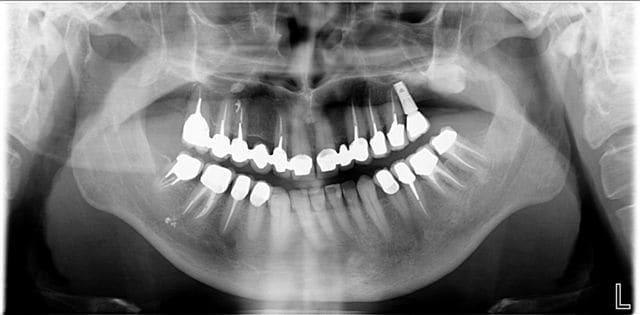

La classe III est alvéolaire ou dentaire , peut-être pas tellement squelettique, mais de face , difficile de juger.

Un peu d'ingression des incisives inf et de vestibulo-version des sup, quelques implants et c'est réglé.

de retour au cabinet je peux vous poster les différentes étapes de ce que j'ai réalisées pour ce patient dans le cadre de l'OSB afin de me faire mousser et non de partager avec vous une expérience qui m'a parue intéressante comme alternative à la cavalerie lourde proposée par certains d'entre vous à savoir la chirurgie...

J'ai reçu ce patient en mai 2006

Tout d'abord évaluation de la hauteur d'occlusion fonctionnelle à l'aide de cire à boxer on laisse le patient avaler sa salive pendant 10 mn, puis arc facial et montage sur articulateur Artex, wax up et reconstitution prothétique temporaire des dents postérieures.

Validation de cette nouvelle occlusion par le patient pendant 6 mois puis si tout baigne prothèse fixe céramique, globale dans ce cas.

Cas terminé en décembre 2006, revu la semaine dernière, ce qui m'a donné envie de vous le montrer.